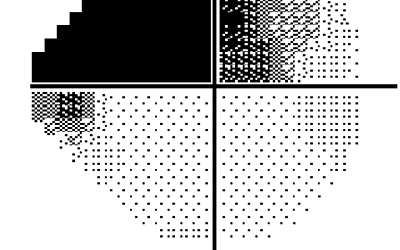

Dégradation du champ visuel au cours d’examens successifs

Les logiciels d'analyse permettent d'évaluer précisément l'évolution du champ visuel des patients glaucomateux. Dans le domaine du glaucome, la décision thérapeutique est directement liée à l’appréciation correcte de l’atteinte structurale et fonctionnelle. Déterminer...